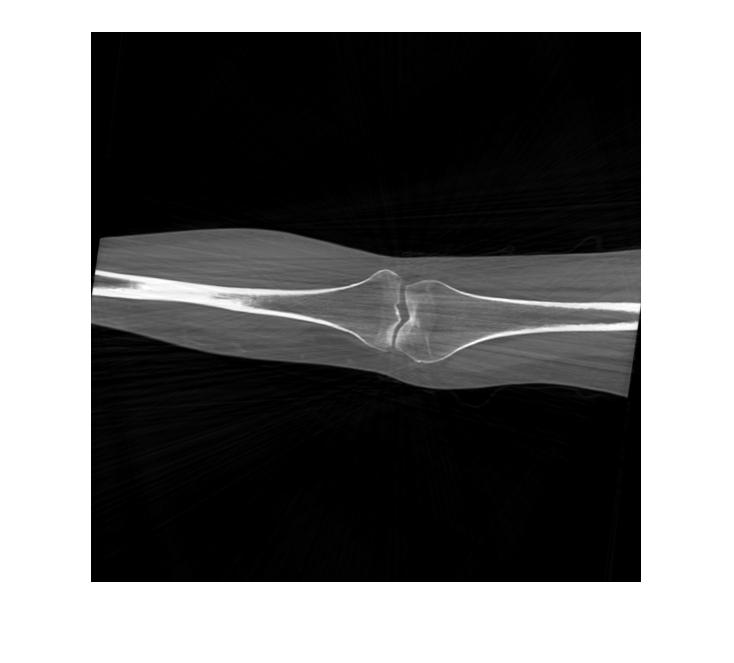

We test our algorithm on the tomographic reconstruction of two objects. The first is the Shepp–Logan phantom, and the second is a computed tomography of a knee taken from Ref. [32]. See Figure 5.6. In this experiment, we generate random points uniformly distributed in . The parameters used in Algorithm 3 are , and . The tomographic projections are computed using Matlab ‘s radon function. We add random noise to these projections, for that, we consider the dataset of the form

In Figures 5.9 and 5.10, we plot the reconstructed images of the Shepp–Logan phantom and the knee tomography, respectively. Here, the samples of the angles are uniformly distributed over . We consider different levels of additive order error as represented in Eq. (5.16). We remark that we obtained similar results to those shown using multiple executions of our method. To measure the effectiveness of our method, we compare the error generated when our algorithm is implemented. The computed error is shown in Tables 1 and 2. Observing the computational error and image quality, we conclude that our reconstruction algorithm works efficiently with relatively low computational cost.